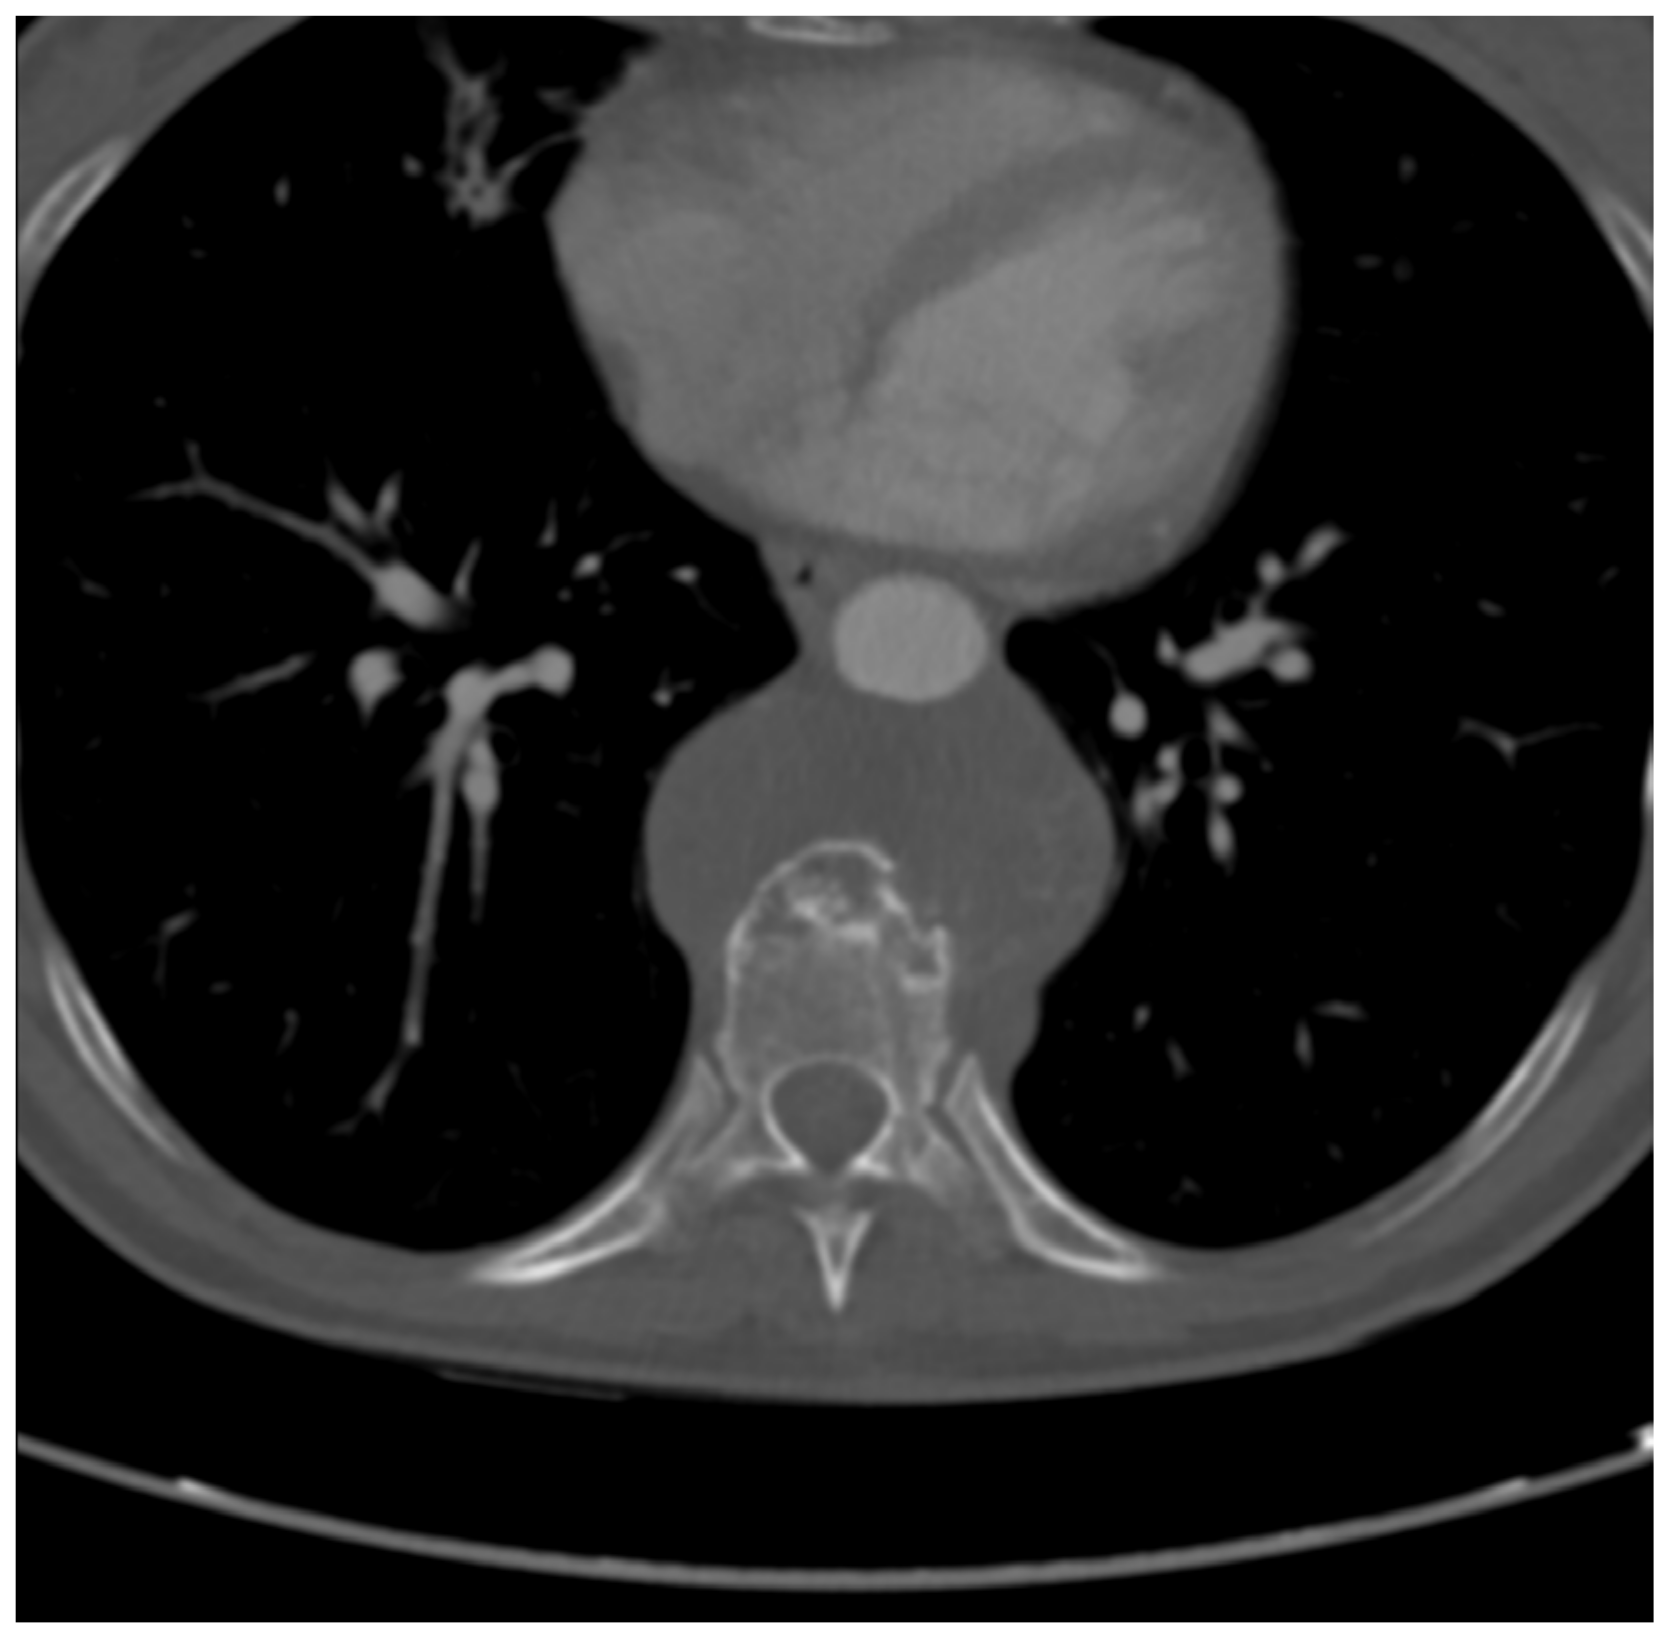

2.2. Imaging Studies

2.7. Post-Operative Period and Follow Up